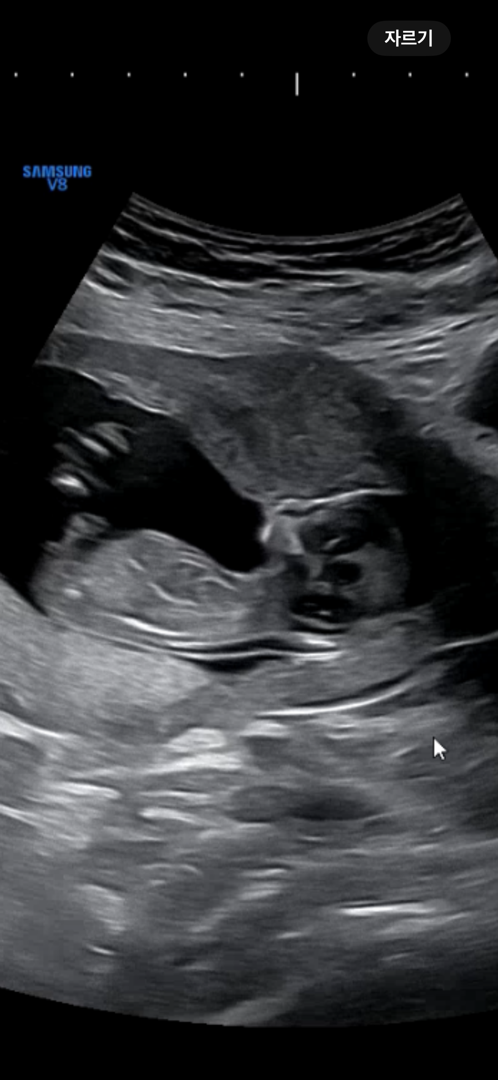

각도법 성별 한번 봐주세요!

12주 4일차입니다! 아들일까요? 딸일까요?

끝이 갈라진 게 맞다면 딸이요..!

아들에 한표요 ㅎㅎ